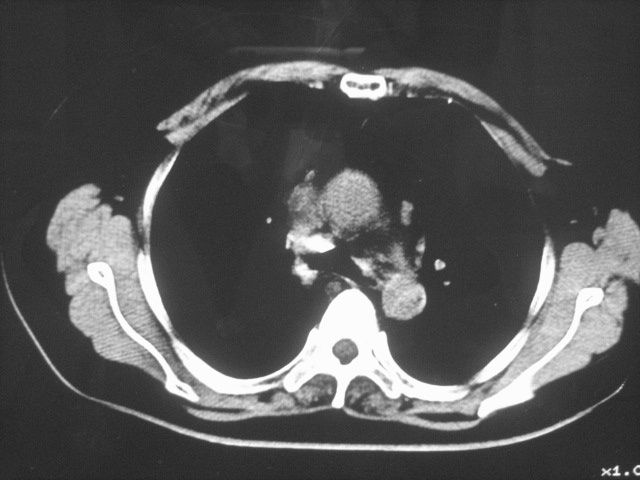

以下是引用清清楚楚在2007-8-28 7:13:00的发言:[br]右肺下叶可见斑片状高密度影,边缘模糊;右肺中叶内侧段及左肺舌段亦可见小斑片状模糊影。[br]考虑双肺感染,建议抗炎治疗后复查。

以下是引用天南地北在2007-8-27 23:49:00的发言:[br]右肺下叶可见斑片状高密度影,边缘模糊;右肺中叶内侧段及左肺舌段亦可见小斑片状模糊影。[br]考虑双肺感染,建议积极抗炎治疗后复查。

以下是引用难听在2007-8-28 13:17:00的发言:[br]右肺下叶背段支气管狭窄,是否可以考虑新生物伴阻塞性肺炎.请大家帮帮忙,这个病人是卫生局长的丈母娘.惹不起啊.